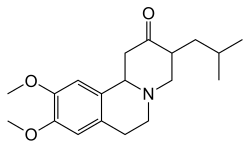

Medications

Tetrabenazine was approved in 2000 for treatment of chorea in Huntington's disease in the EU, and in 2008 in the US.[92] Although other drugs had been used "off label", tetrabenazine was the first approved treatment for Huntington's disease in the U.S. The compound has been known since the 1950s. In 2017, deutetrabenazine, a heavier form of tetrabenazine medication for the treatment of chorea in HD, was approved by the FDA.[93] This is marketed as Austedo. Valbenazine (Ingrezza) was also approved by the FDA for the treatment of Huntington's disease chorea in 2023.[94] Tetrabenazine, deutetrabenazine, and valbenazine are all vesicular monoamine transporter 2 (VMAT2) inhibitors, which work by depleting dopamine in the brain, lessening involuntary movements.[95] These are the only drugs that have been approved specifically for Huntington's disease (namely the chorea associated with it).

Other drugs that help to reduce chorea include antipsychotics and benzodiazepines.[26] Hypokinesia and rigidity, especially in juvenile cases, can be treated with antiparkinsonian drugs, and myoclonic hyperkinesia can be treated with valproic acid.[26] Tentative evidence has found ethyl eicosapentaenoic acid to improve motor symptoms at one year.[96] Amantadine has also been used to treat chorea, but there is limited evidence for its safety and efficacy.[97]